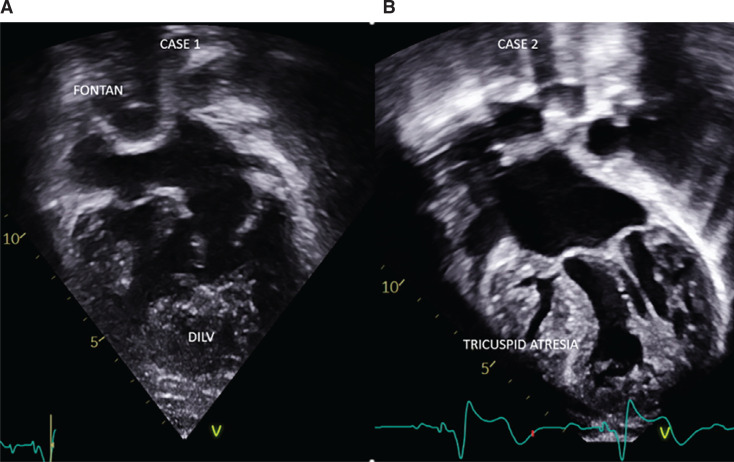

Current leadless pacemaker (LP) systems, which have been developed and used in patients with normal cardiac anatomy, are rare and technically even more challenging to implant in patients with congenital heart diseases, especially with univentricular physiology and Fontan palliation. We report two cases of percutaneous LP implantation in an adult and a child, respectively, highlighting the unconventional approaches, different challenges, and use of multimodality imaging in patients who underwent a Fontan operation.